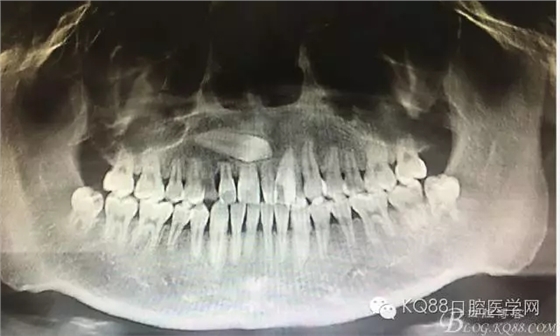

圖1.患者術(shù)前的全景片影像檢查:13位于11、12之間。全景片無法得知13到底在唇側(cè)還是腭側(cè)。